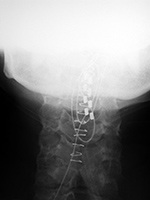

| Zero-Profile lumbar fixation L2-L5 |

| 45 year-old woman with L2-5 anterior lumbar interbody fusion (ALIF) for low back pain. The lateral views are respectively in neutral and flexion positions. The CT images are selected slices in the coronal and sagittal planes, respectively. |

| 45 year-old woman with L2-5 anterior lumbar interbody fusion (ALIF) for low back pain. |